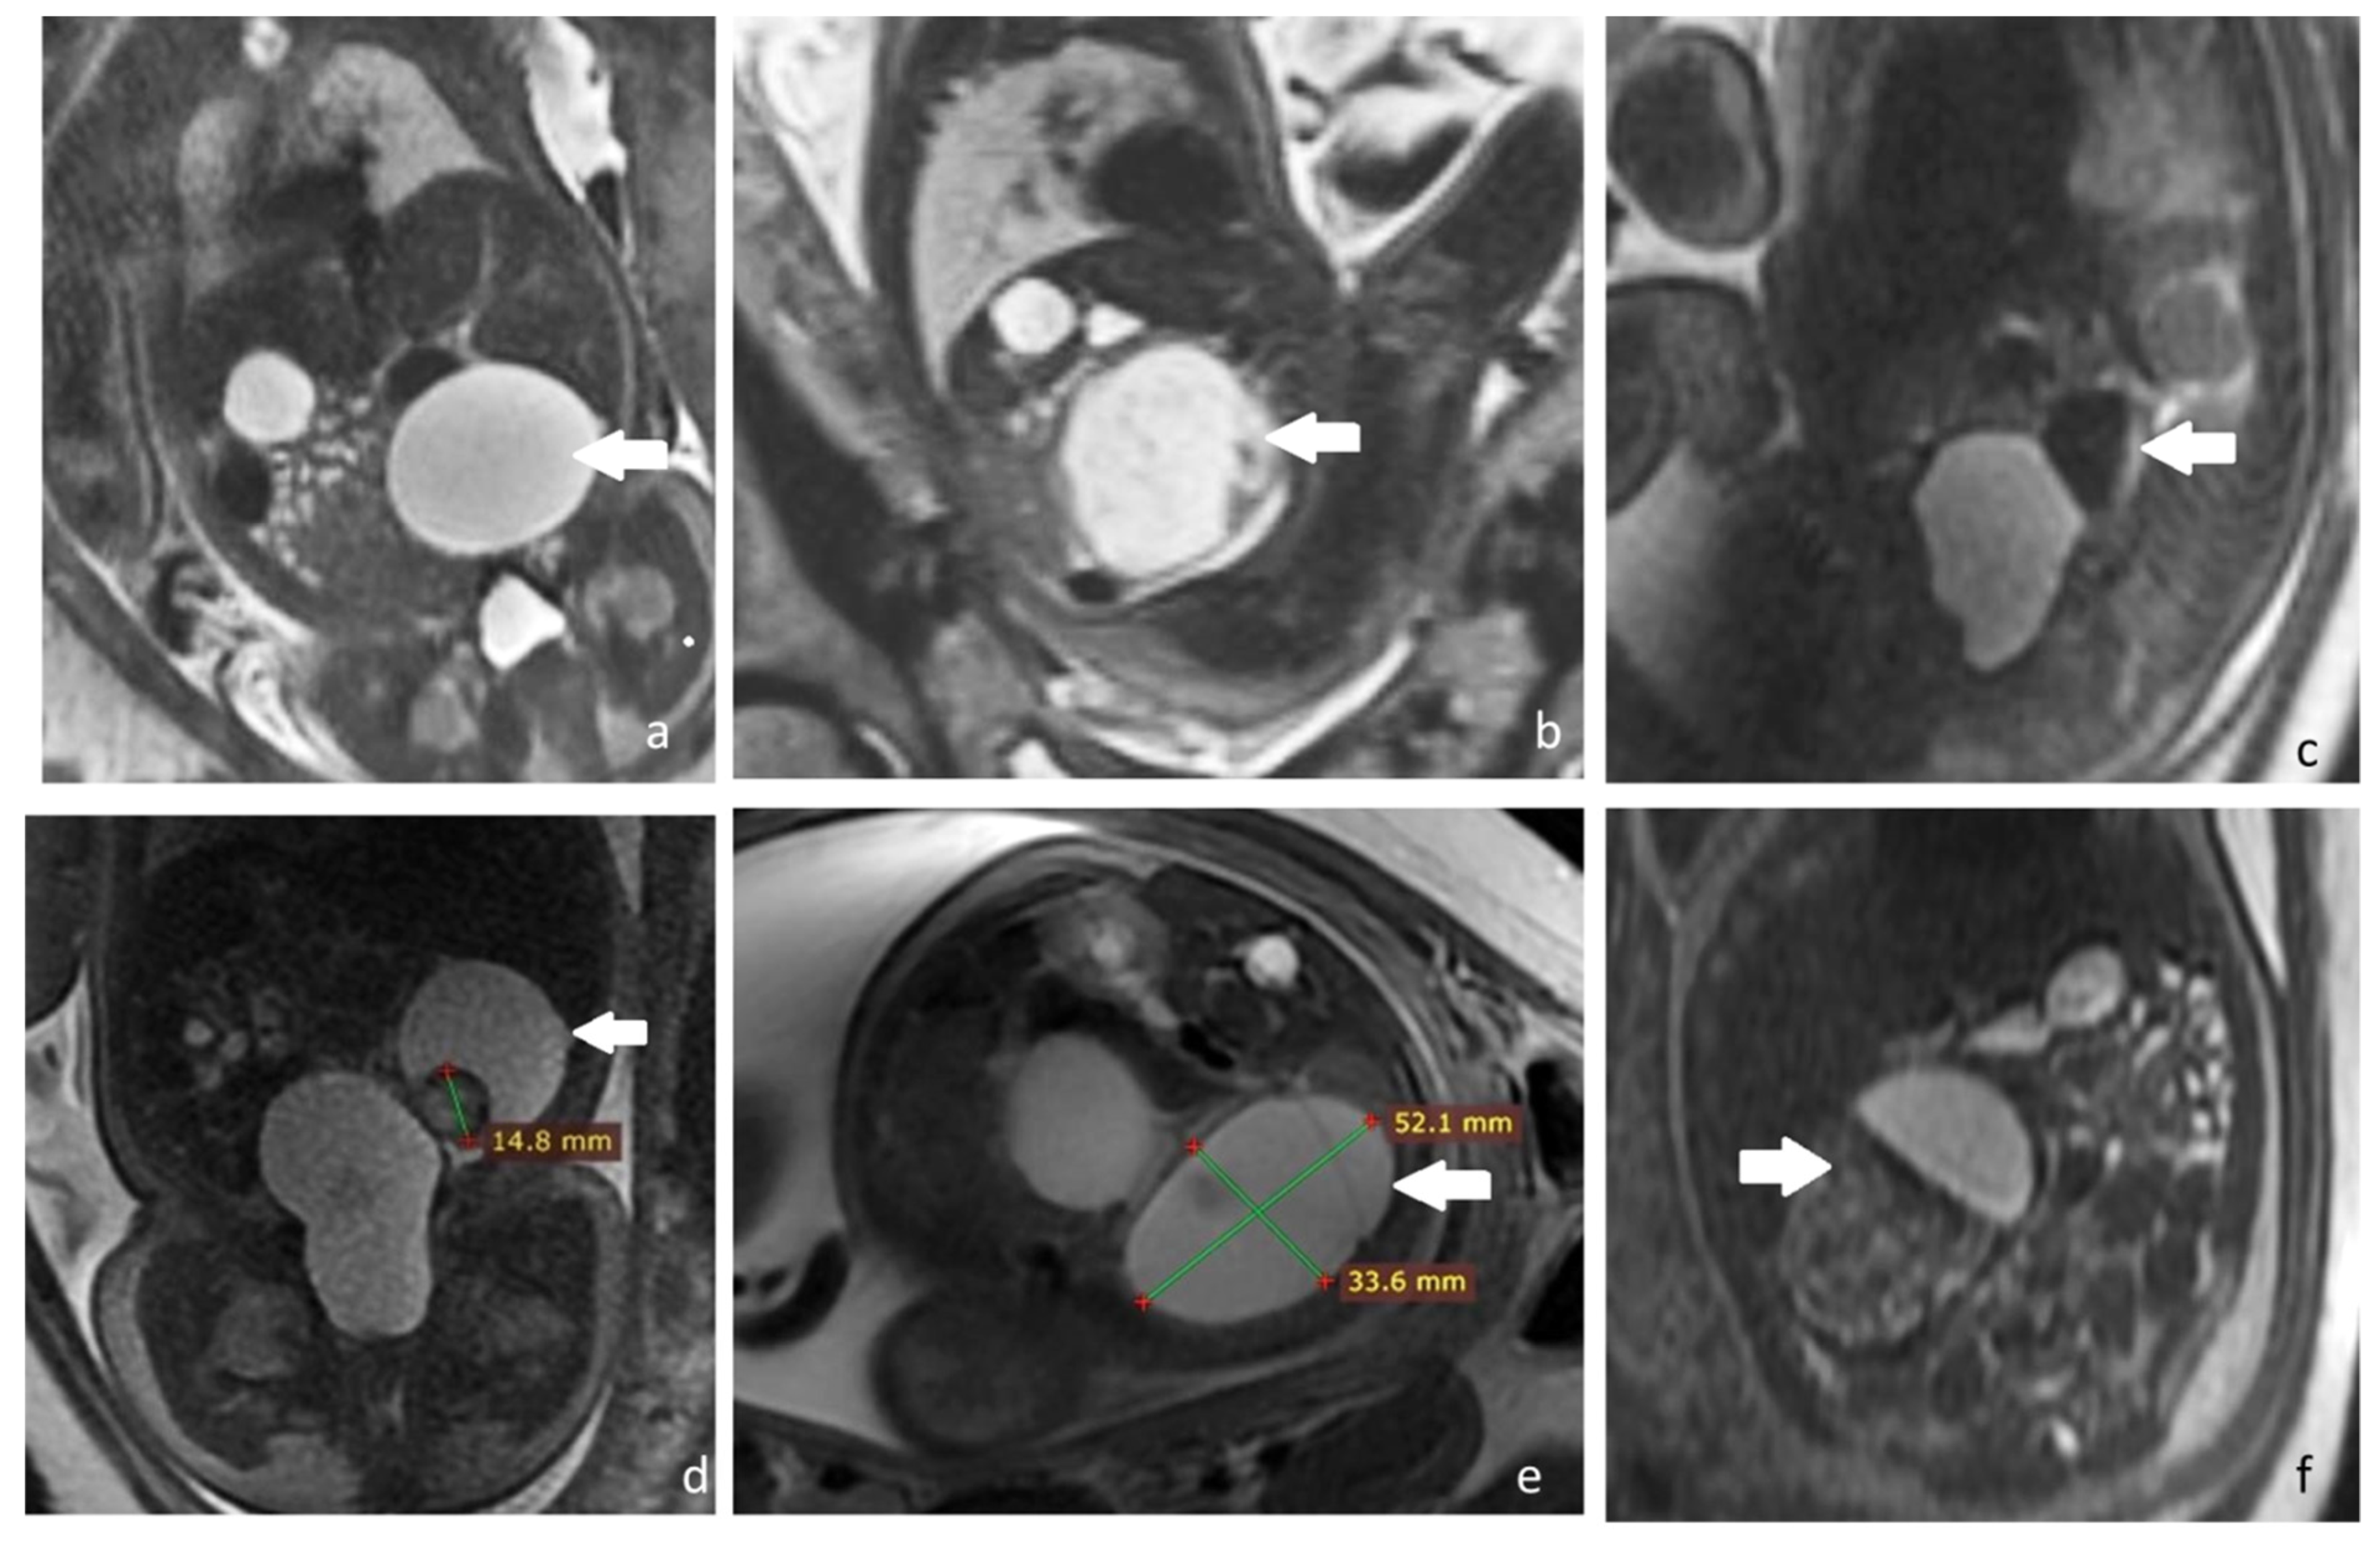

Still, three out of the five cases with recommended postnatal clinic and imagistic follow-up required emergency surgical treatment for ovarian torsion, intracystic hemorrhage, and peritonitis within the first six weeks after birth. In addition, in one case an exploratory surgical intervention for the suspicion of enteric duplication was performed, finding a self-amputated ovarian cyst, presence of which was suspected from week 31 of gestation. Only one case diagnosed antenatal with a simple 4 cm cyst presented spontaneous resorption within six months after delivery (Figure 3).

Figure 3. Consecutive prenatal ultrasonography depicting transformations of a fetal ovarian cyst that presented postnatal resorption, discovered at 31 weeks of gestation, and follow up until 36 weeks of gestation in a woman diagnosed with severe preeclampsia. (a) Thirty-one weeks of gestation female fetus with an 3 cm diameter echogenic right ovarian cyst with a thing wall, suggesting intracystic hemorrhage; (b) 32 weeks and 4 days, the changes of the cyst are followed, which becomes elongated, keeping the appearance of a intracystic hemorrhage, measuring 4.5/4 cm; (c) same case at 33 weeks and four days the fetal cystic begins to clarify its contents and maintains its decreases it diameter at 4.5/3.5 cm (d) same case at 36 weeks and four days, the fetal cyst is in important resorption measuring 2.32/2.39 cm. Figure 3a,c,d represent B-mode ultrasound images, while Figure 3b is CFM (Colour Flow Mapping) ultrasound mode that shows peripheral blood flow.